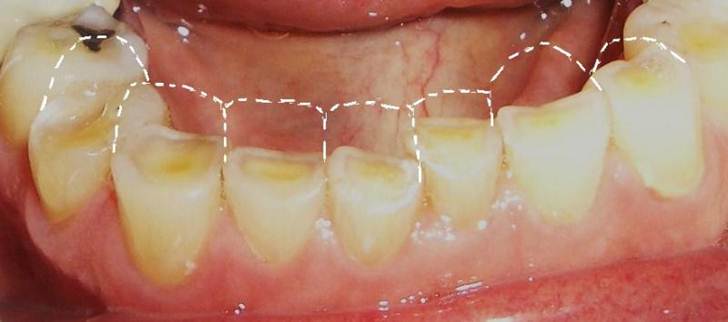

Acid wear may lead to serious dental problems. It is important to notice the signs of tooth erosion in its early stages (sensitivity and discoloration) before more severe damage occur, such as cracks, pain and decay.

• Discoloration. Teeth can become increasingly yellow as the thinning enamel layer exposes the underlying dentin.

• Rounded teeth. Your teeth may have a rounded or "sand-blasted" look.

• Transparency. Your front teeth may appear slightly translucent near the edges.

• Cracks. Small cracks and roughness may appear at the edges of teeth.